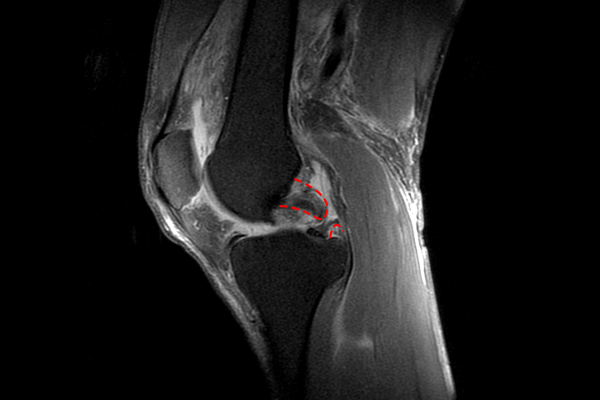

무릎의 뒤쪽에서 확인할 때의 내시경 사진입니다. 후방십자인대가 파열되어 보이지 않고 잔해만 남아있는 것이 확인됩니다.

뼛조각도 같이 떨어져 나온 것이 확인되어, 뼛조각을 제거해줍니다.